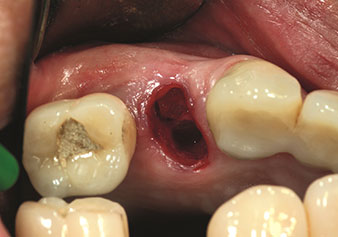

Situation following piezosurgical extraction

Fig. 2: Situation following piezosurgical extraction. Photo: © Dr Torsten Conrad (Bingen am Rhein)